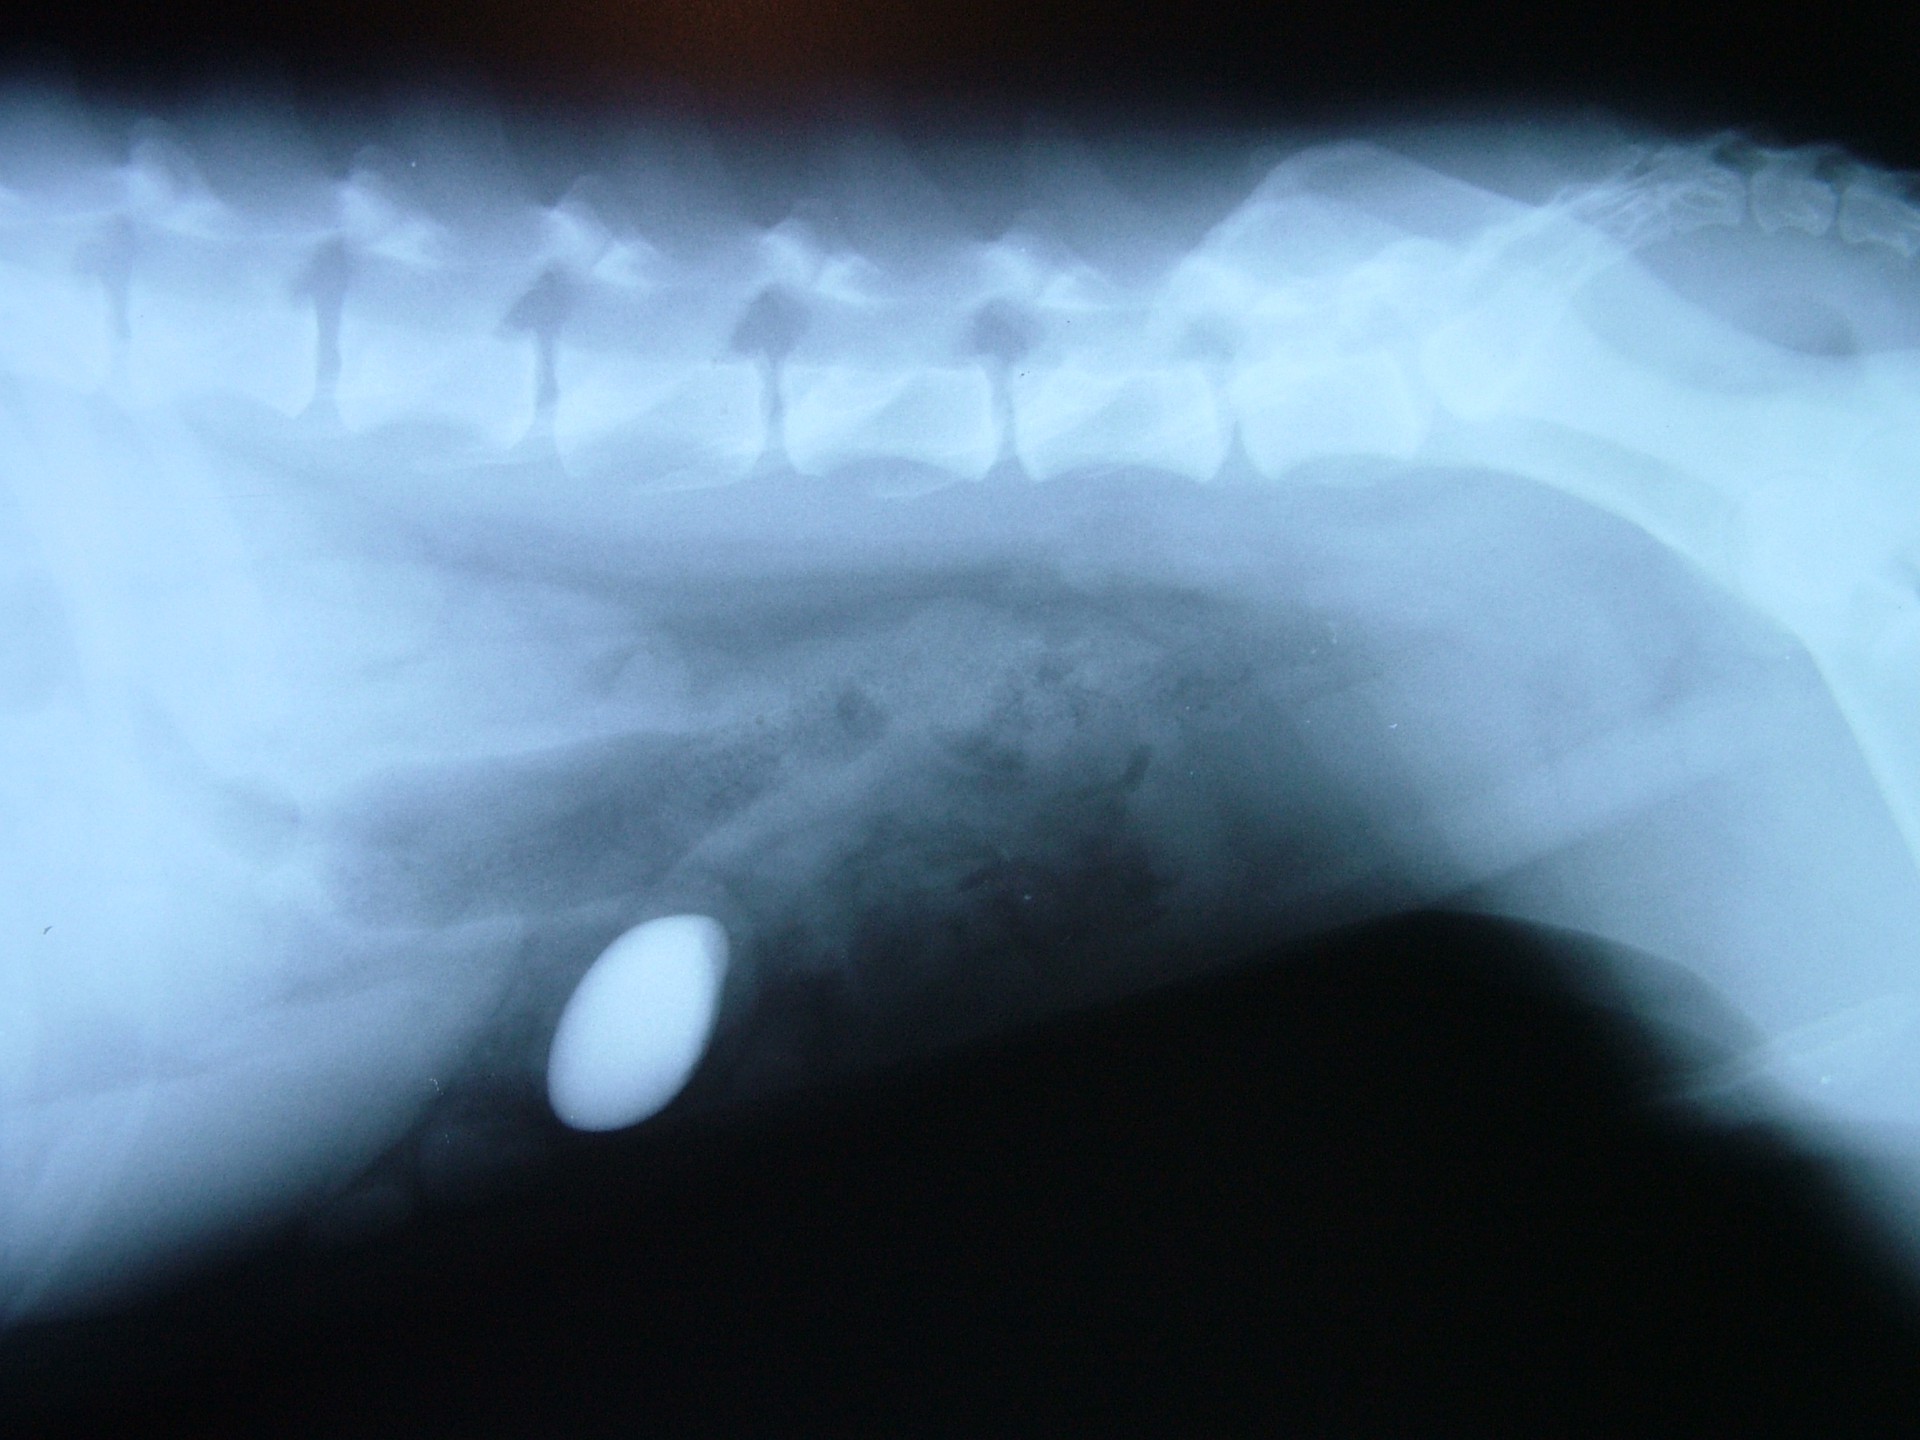

• A bélcsatorna eltömődése (ileus obturationis): általában idegentest (kő, gesztenye, barackmag, műanyag játék stb.) lenyelése következtében kialakult elváltozás. A lenyelt képlet a gyomorból a vékonybélbe jutva a bél lumenét részlegesen (subileus) vagy teljesen elzárja megakadályozva ezzel a béltartalom tovább haladását. Obturatios ileus alakulhat ki béldaganatok esetében is, de ilyenkor a klinikai tünetek megjelenése a daganat növekedésének megfelelően lassan következik be.

A különféle bélelzáródások diagnosztikája során a kórelőzmény (pl.: játék lenyelése) és a klinikai tünetek (hányás, a has feszítése, tapintható idegentest a hasüregben stb.) mellett kiegészítő vizsgálatként RTG vizsgálat és a hasüreg ultrahangos vizsgálata jöhet szóba. A bél elzáródását okozó képletek az esetek döntő többségében nem adnak röntgen árnyékot, ezért un.: röntgen kontrasztanyagot etetünk az állattal és többszöri röntgenfelvétel készítésével figyeljük a tovahaladását.

Abban az esetben, ha a kontraszt anyag elakad, az ileus diagnózisa nagy biztonsággal kimondható. Ultrahangos vizsgálattal a bélelzáródás előtti területen felhalmozódó béltartalom un.: inga-mozgása is egyértelműen bélelzáródásra utaló diagnosztikai jel.